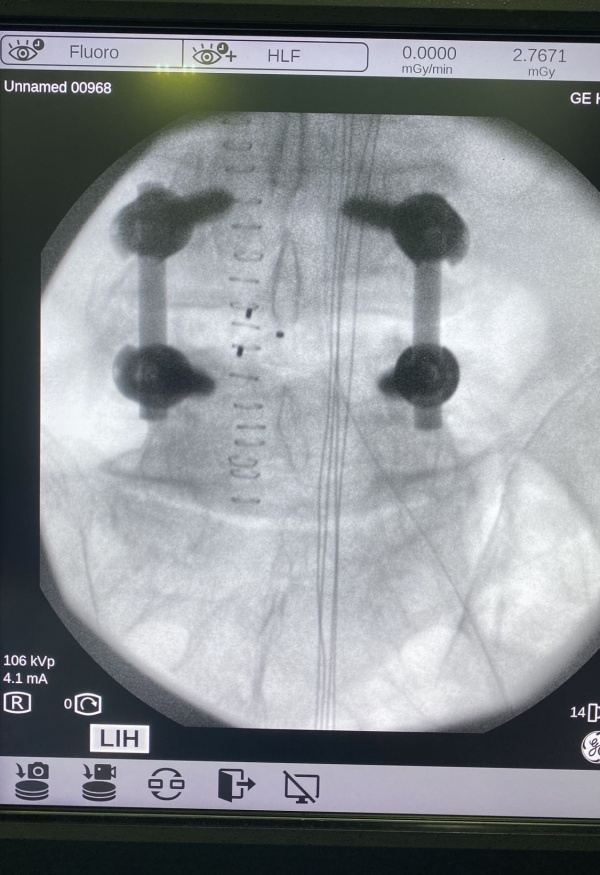

ESTENOSIS DE CANAL LUMBAR: para la resolución de este importante problema debemos liberar el canal lumbar, que se encuentra estrechado con compresión de las raíces nerviosas o la médula y en función del caso, realizar una ARTRODESIS VERTEBRAL (fijación de las vértebras para que no recidive la lesión). Este tipo de cirugía precisa ingreso de 4-5 días y la recuperación va desde 6 semanas a 3-4 meses por lo general.

Artrodesis lumbar